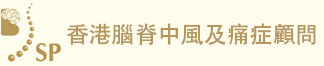

再者,比喻說我們人體就如一部汽車,政府規定汽車每一年都要例行檢查汽車的零件,看看是否安全行駛,不會在駕駛中失去安全操作而發生意外。然而,抽血檢查就像放取汽車偈油來檢查一樣,不能反影汽車內部零件的耗損和安全性。那麼要防止人體腦中風意外的發生, 就是不能單單透過抽血檢驗,而是要利用三維立體腦血管造影,作出詳盡的人體零部件篩查。如果例行的身體檢查包括了三維立體腦血管造影,腦神經外科醫生就可以在患者沒有症狀之前,找出先天性或後天性的計時炸彈,在其未爆發前將其拆除,來避免中風。

兩位分別是16歲的少年和56歲的男士,在沒有任何徵象之下做了詳盡的身體檢查,三維立體腦血管造影顯示兩人的大腦都有先天性的腦血管動靜脈畸形,在專科醫生建議之下透過了一段時間的觀察和保守治療,其後利用了微創內血管治療加上放射治療,畸形血管得到了有效的根治,病人與生俱來的大腦炸彈得到了拆除,減低了他們將來出血性中風的可能性。